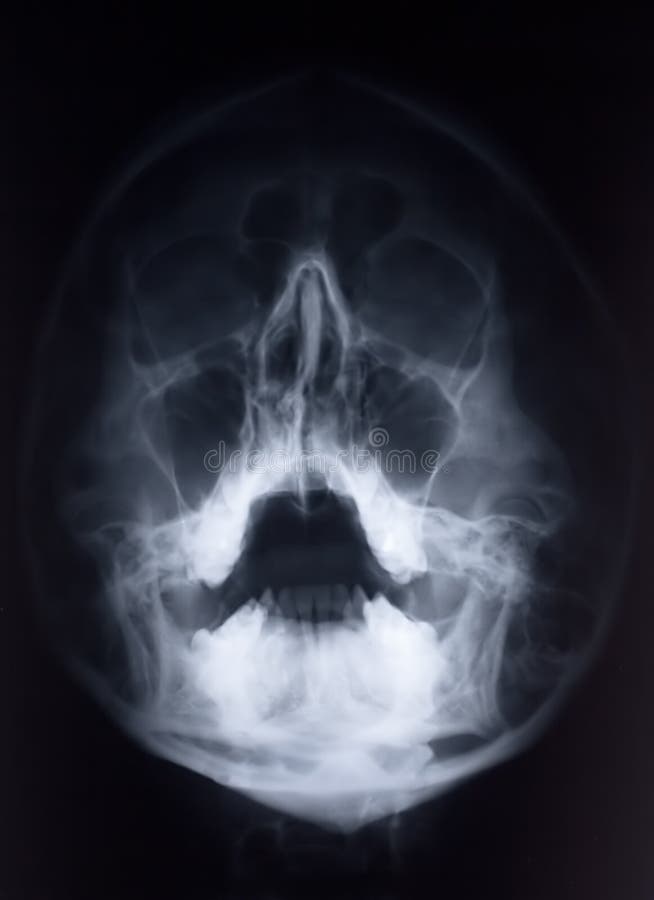

Parte Dianteira Do Raio X/face Foto De Stock - Imagem: 198830

raio dianteira xray raggi anteriore fronte opinião parti ossa

Parte Dianteira Do Raio X/face Imagens De Stock Royalty Free - Imagem

raio dianteira opinião xray